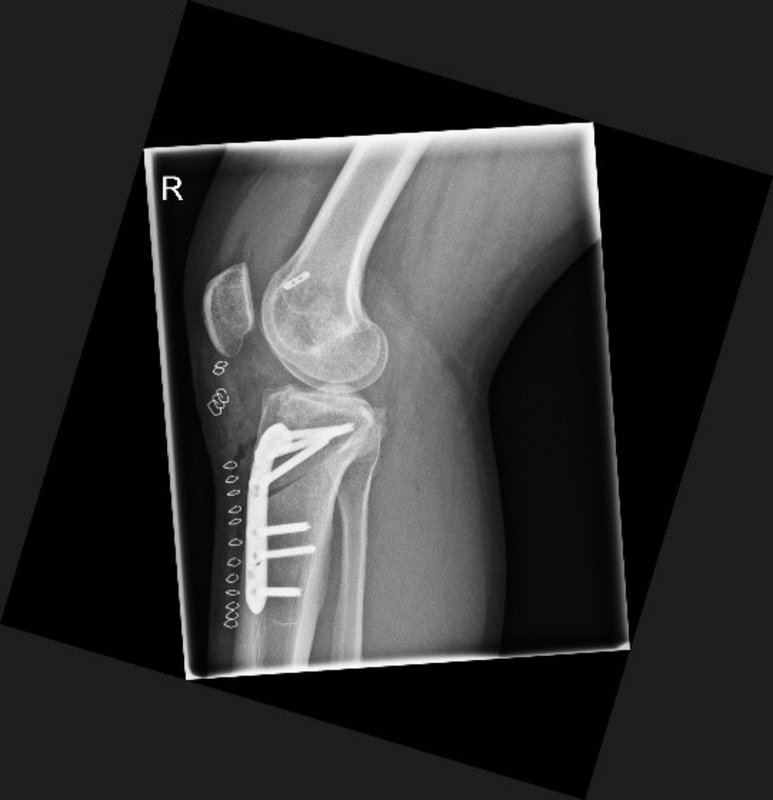

Tibiakopf Fraktur

Die arthroskopisch assistierte Frakturversorgung (insbesondere am Tibiakopf) im Rahmen von Band- bzw. Kombinationsverletzungen ist ebenfalls ein Schwerpunkt der Abteilung. Der ärztliche Direktor PD Dr. med. Schlumberger ist im DKG-Komitee „Frakturen“ vertreten.